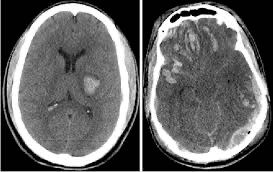

A diagnosis is confirmed using brain imaging, most commonly a CT scan. An MRI scan may be used in selected cases. Anyone who has suffered a significant head injury should seek medical attention.